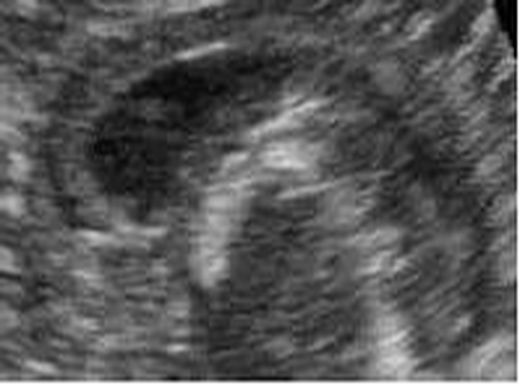

The project deals with ultrasound images processing. It focuses on ultrasound images of premature infants’ brains.

• Boundary Detection in US images using Geodesic Active Contour Model

As in other cases of dealing with images, also in medical images, like US images, we use image processing and computer vision techniques to analyze those US images for numerous tasks.